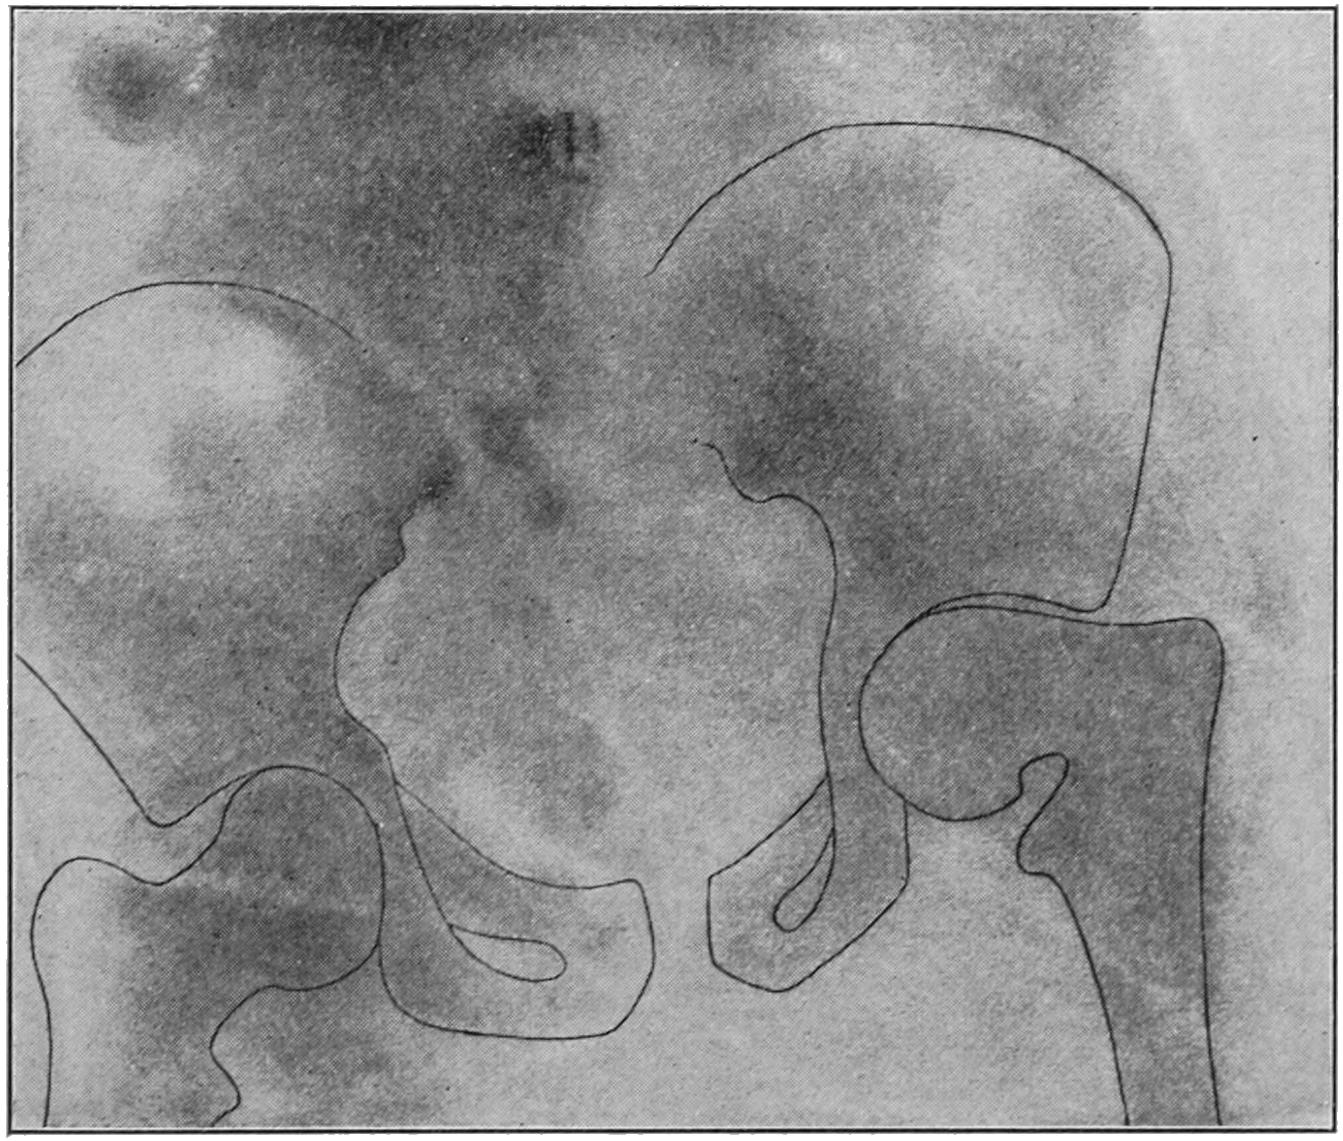

Fig. 1

Congenital hypertrophy: gigantism of both lower extremities. (Case of Dr. Graefe [Sandusky].)